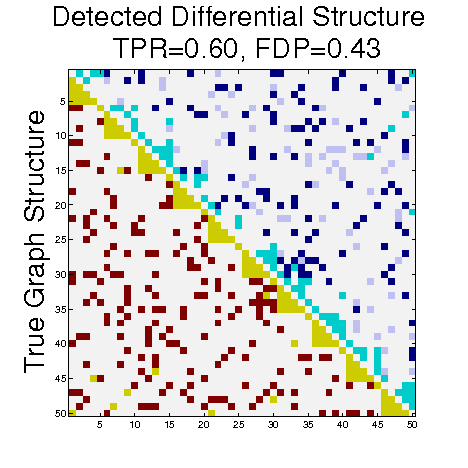

To understand the performance of this standard method, we present a small preview of our simulation study discussed later in Section 4. Briefly, we assume that each subject graph in group follows a small-world structure on nodes; in group , there are in addition 150 differential edges, meaning that and for all differential edges, . We generate data according to this model with time points and subjects in each group. Figure 1 illustrates the results of this standard approach as well as our new procedure, , which we will introduce later in Section 3. Part (a) gives ROC curves for the number of false positives verses true positives as each sequential test is rejected; parts (b) and (c) give the adjacency confusion matrix illustrating where the true and false positive as well as false negative edges are detected in the graph structure.

Our motivating simulation shows that the standard approach performs terribly in terms of both error control and statistical power. While the magnitude of the poor performance of this approach may seem astonishing, the poor performance should come as no surprise: The inferential procedure (e.g. test statistics) of the standard approach assume a one-level model that would be appropriate when the subject graphs are fixed and known or directly observed quantities. When these subject networks are unobserved, however, and must be estimated from finite data, these one-level test statistics are incorrect for our two-level problem. Specifically for two-level problems, the variance of parameters estimated by incorrectly assuming a one-level models is underestimated. For our problem, the extra source of variability arises from the graph selection procedure; we discuss challenges associated with this subsequently in Section 2.2. Incorrect variance estimates, however, are not the only problem with the standard approach: A more subtle problem arises from the fact that the proclivities of graph selection procedures for the Gaussian graphical model lead to biased estimates of the edge proportions, . As discussed in Section 2.3 and seen in Fig 1, graph selection false positives and false negatives do not occur at random throughout the network structure, leading to biased group level estimates.

Hence, the first term represents variability across subjects in group and the second term represents the variability associated with the selection procedure within subject , a quantity that we assume to be constant across subjects in each group . Consider now what happens if our true model follows this two-level Beta-Binomial model, but as with the standard approach, we use a one-level Binomial model and associated two-sample test statistic. The variance is thus underestimated and the test statistic is overoptimistic. Then, when inference is conducted for the population mean , using the incorrect Binomial model leads to inflated Type I error rates; this behavior has been well-documented (Weil, 1970; Liang and Hanfelt, 1994). Hence, failure to use the correct two-level model which accounts for the two levels of network variability partially explains the high error rates of the standard procedure observed in Figure 1.

Henceforth, we will denote the components of as Resampling (RS), Random Penalization (RP) and Random Effects (RE). To better understand how each challenge outlined in Section 2 as well as the our methodological solutions to these challenges affect inferential procedures, we compare not only to the standard approach but also variations of our own method: with (RS, RP) and with (RS,RE). Recall from Section 2, that the standard approach uses two-sample test statistics associated with the one-level Binomial distribution. Both the numerator and denominator of this test statistic are incorrect, with the mean group level parameters biased by graph selection errors (Challenge II in Section 2.3) and with the denominator under-estimating the variance components associated with two levels of network variability (Challenge I in Section 2.2). Our first variant, (RS, RP), seeks to address only Challenge II by ameliorating the bias in group-level edge proportions using random penalization. Our second variant, (RS, RE) seeks to address only Challenge I by using the correct two-level Beta-Binomial model and test statistics. We adopt the same specifications outlined in Section 3.5 with selected using StARS (Liu, Roeder and Wasserman, 2010) for all methods. Methods including the RE component use random effect statistics from Section 3.4, while those without RE use the standard two-sample binomial proportions test as in Section 2.2. We control FDR at 10% for all methods using the Benjamini-Yekutieli approach (Benjamini and Yekutieli, 2001).

In Figure 4 and Table 1, we present our main simulation results comparing to the two variations of our method and the standard approach for three network structures and Case I and II type differential edges. First for Figure 4, we report results in terms of operating characteristics averaged across 50 replicates with the number of true positives (y-axis) plotted against the number of false positives (x-axis) for each test statistic, rejected sequentially from largest to smallest in absolute magnitude. Overall, all of our methods and particularly yield substantial improvements over the standard approach in all scenarios.

Notice that both and =(RS,RP) share similar orderings of test statistics, and consequently similar ROC curves. Overall, methods that include random penalization yield major improvements in statistical power over those that do not. This indicates that the second popPSI challenge outlined in Section 2.3 is a significant contributor to the poor performance of the standard method. Recall our discussion of how graph selection errors at the subject stage occur non-randomly and hence bias our group-level estimates of . Our results empirically demonstrate that random penalization dramatically improves these biases, leading to less bias in our test statistics and hence improvements in both Type I and Type II error rates. Furthermore, in Case II scenarios where selection errors are moderate, the performance gap between any method containing over reduces compared to Case I scenarios where selection errors are more severe. Thus, the benefits of random penalization are greater when selection errors are more abundant. Confusion adjacency matrices illustrating the location of inferential errors for our methods shown in the supplemental materials also indicate that random penalization improves graph selection in cases where there are larger correlations between differential edges and common edges. Similar results hold for our high-dimensional study presented in the supplemental material.

Table 1, which accompanies Figure 4, gives the empirical true positive and false discovery rates (FDR) averaged over 50 simulation replicates when the Benjamini-Yekutieli (Benjamini and Yekutieli, 2001) procedure controlling the FDR at 10% is used to determine the number of tests to reject. First, notice that the observed false discovery proportion (FDP) of our procedure is not 10% on average, indicating that our method does not fully control the FDR. This occurs because we specifically simulate difficult and realistic fMRI scenarios with graph structures that severely violate irrepresentable-type conditions. In situations (not shown) where irrepresentable-type conditions are met that ensure graph selection consistency, our procedure as well as the standard method correctly control the FDR. As discussed in Section 2.3, in situations where graph selection errors occur with high probability, it is likely impossible to provably control the FDR, consistent with our empirical results. Yet even though does not fully control the FDR, our error rates are dramatically improved over the standard approach and other variations of our procedure.

Also in Table 1, observe that (RS,RP), which had similarly ordered test statistics to , has dramatically worse Type I error rates that do not come close to controlling the FDR. While (RS,RE) also does not control the FDR, the error rates are much improved over (RS,RP). These results demonstrate that using two-level models with the correct random effects test statistics are crucial to Type I error control. Recall from Section 2.2, that using the one-level Binomial model leads to an under-estimation of the variance term which in turn inflates test statistics and leads to an increase in false positives. Note also that the estimated FDP of is still a major improvement over that of (RS,RE). This occurs as the problem of graph selection errors induces both Type I and Type II errors. Hence, these results demonstrate the necessity of all three of our ingredients. Finally, observe that our error rates in Case II scenarios are better than those for Case I scenarios, again indicating that differential edges that are highly correlated with non-edges and common edges pose particular challenges for our popPSI problem. These results are also corroborated in our high-dimensional study presented in the supplemental materials.